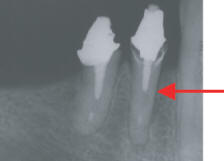

Fig. #2: Caso remitido para

Retratamiento en el que se observa radiográficamente (debido a

ausencia de material de obturación) una línea de Fractura Vertical

en una toma ortoradial. |